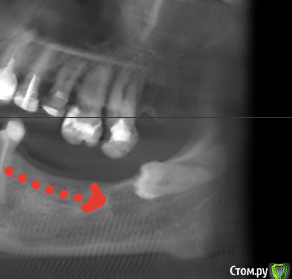

Sergiosse Опубликовано 16 февраля, 2017 Поделиться Опубликовано 16 февраля, 2017 (изменено) Планирую имплантировать в обл. 7 зуба.Смущает разрежение вокруг коронки 8 -го. Удалять или ....? И еще засада , на срезах не видно границ н.ч. канала.Остеопороз? Какие анализы делать в таких случаях? Изменено 16 февраля, 2017 пользователем Sergiosse Ссылка на комментарий

Irouil Опубликовано 21 февраля, 2017 Поделиться Опубликовано 21 февраля, 2017 По поводу канала - покажите клкт, на этом снимке вроде все видно. Сам по себе остеопороз не катастрофа. Что касается восьмерки - ну конечно удалять. Ссылка на комментарий